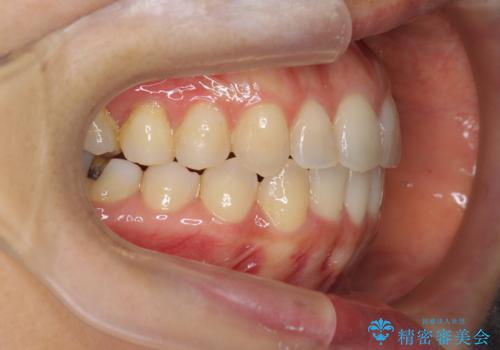

前歯のガタつきをマウスピースで治したい!

- 気になる前歯のガタつきをマウスピースで治療したいと希望され来院されました。

当日に矯正検査を行い、骨格・歯に問題がないことを確認しマウスピースによる矯正治療を進めます。

IPRを前歯部に少量行うことで、非抜歯でも前歯が外に飛び出さない仕上がりを達成できました。